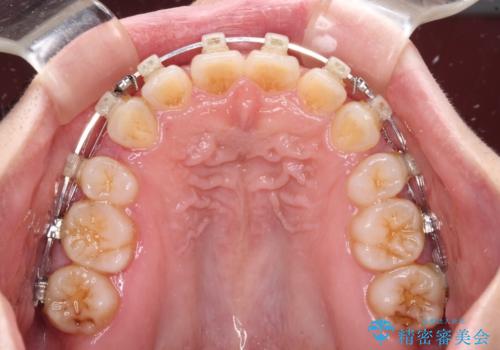

- クリアブラケット

上下ともに顎が小さく、歯列が前方に突き出していたため、上下左右の第一小臼歯4本を抜歯し、口元の突出感を改善していくこととしました。